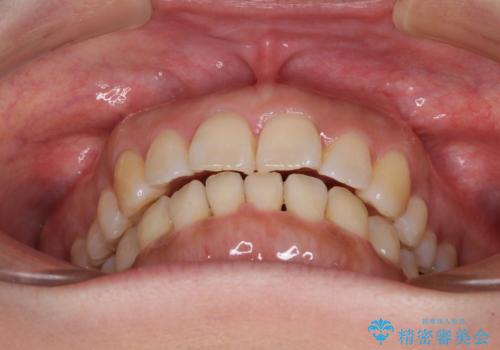

- 上下前歯の叢生を気にして来院された患者様です。

費用を抑え、期間もあまりかけずに治療をしたいとのことで、インビザライン・ライトを用いて矯正治療を行うこととしました。